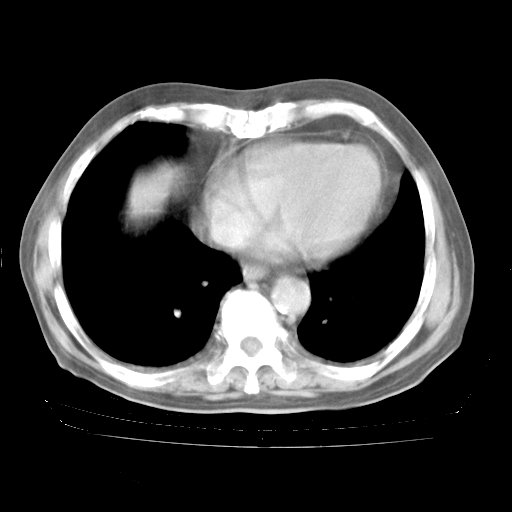

4月28日肺部CT——再次出现类似去年5月9日——透光度降低,“间质性”改变。

4月28日肺部CT——再次出现类似去年5月9日——磨玻璃样、间有“粟粒样”改变。